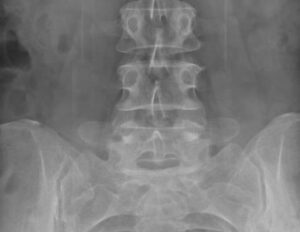

Рентген копчика: особенности проведения диагностики

Пациентам, которые жалуются на боли в пояснично-крестцовом отделе позвоночника, проводят рентгенографию копчика. Дискомфорт возникает как после травмы, так и независимо от нее, как следствие патологии опорно-двигательного аппарата. Узнать, почему возникают проблемы с копчиком, поможет рентгенологическая диагностика. Подготовка к рентгену позвоночника и проведение исследования Диагностика не требует длительной подготовки к рентгенологическому исследованию копчика. Накануне процедуры врачи …